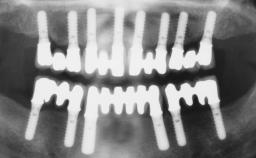

Immediate Implant Placement and Immediate Provisionalization with a Prefabricated-Shell Provisional Crown

In this case, Arndt Happe describes how he achieved a stable outcome at 5 years by giving careful attention to the coronal aspect of the transmucosal area of the provisional, creating a slim emergence profile.

Timing of placement Immediate Placement (extraction sockets) (Type I)

Available apical bone to achieve primary stability Sufficient height ( ≥ 4 mm) and width (> 2 mm around apex of planned implant)

Socket walls Intact

Thickness of buccal wall less than 2 mm

Anticipated residual defect after implant placement 2 mm or less